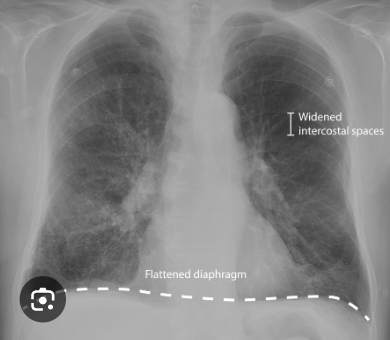

Señor 75 años fumador de oaxaca, tiene un puesto de pollos a la leña. Acude a consulta por una tos seca, IMC inferior a 18.5, disnea de esfuerzo.

Tiene una tez rosada. Determinas que tiene una patología en la que hay un atrapamiento aereo en alveolos sin intercambio gaseoso (entra facil, sale dificil). Tomas una Rx y encuentras el sigueinte hallazgo:

Sospecha diagnóstica:

*torax en tonel & def alpha antitripsina

Efisema

EPOC mas frecuente aosciado a Tabaquismo